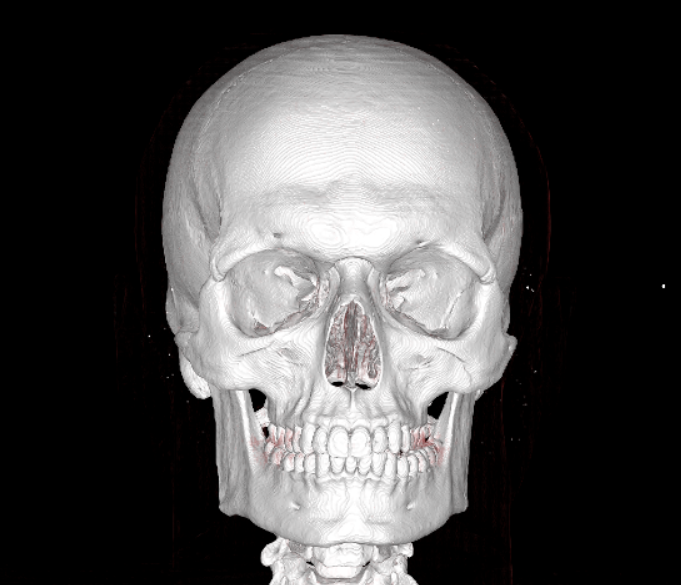

Here are the predicted CT Scans with the Genioplasty:

Here are the predicted CT Scans with the Genioplasty: